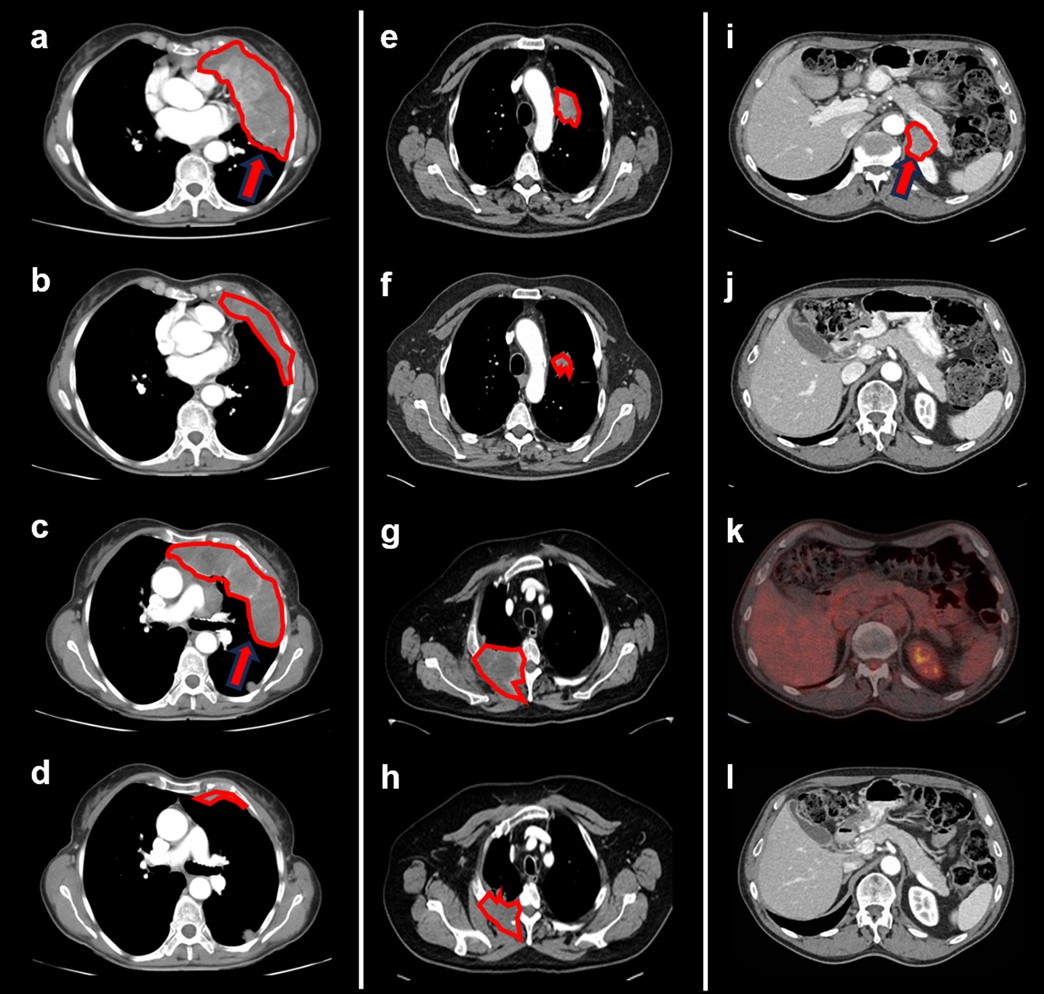

Extended Data Fig. 7: CT and PET-CT scans of responding tumours.

(a-d) Participant with mesothelioma and large, bulky disease (phase 1 part). RECIST 1.1 response under treatment with partial response (a) and (c) show baseline tumour assessment with bulky disease in upper mediastinum at two levels. (b) and (d) show respective significant tumour reduction at corresponding scan level at Cycle 8, Day 1 (week 16). (e, f) Participant with metastatic non-squamous NSCLC, Baseline (e) vs. Cycle 12 (f) demonstrating partial response as per RECIST 1.1. (g, h) Participant with metastatic non-squamous NSCLC (phase 2a part). Baseline (g) vs. Cycle 35 with partial response (h) as per RECIST 1.1. (i-l) Participant with metastatic urothelial cancer (phase 2a part), shown is large retroperitoneal lesion. RECIST 1.1 response with −100% reduction (complete response). (i) Baseline assessment at Screening with lesion marked by red arrow and red line. (j) Cycle 5 Day 1 assessment: Partial response. (k) PET-CT at Cycle 28 Day 1 demonstrating complete metabolic response. (l) CT scan at Cycle 45 Day 1 with continued complete response.